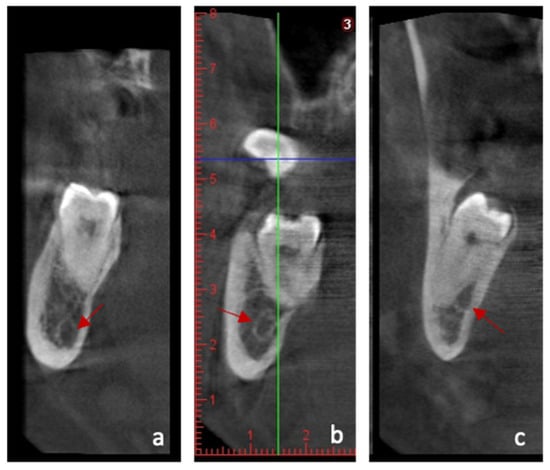

Prevalence and Radiographic Patterns of Impacted Third Molars in a Portuguese Population: A Retrospective Orthopantomography (OPG) and Cone-Beam Computed Tomography (CBCT) Study

by Ana Catarina Pinto, Helena Francisco, Maria Inês Charro, Duarte Marques, Jorge N. R. Martins and João Caramês

Background/Objectives: Impacted third molars are frequent and may increase surgical complexity, particularly when the mandibular third molar is in close proximity to the inferior alveolar canal (IAC). This study aimed to estimate the prevalence and impaction patterns of third molars in a Portuguese [...] Read more.

Background/Objectives: Impacted third molars are frequent and may increase surgical complexity, particularly when the mandibular third molar is in close proximity to the inferior alveolar canal (IAC). This study aimed to estimate the prevalence and impaction patterns of third molars in a Portuguese population and to characterize, using a nested CBCT subsample, the three-dimensional relationship between mandibular third molars and the IAC, including cortical integrity and lingual plate thickness. Methods: A retrospective observational analysis of 1062 orthopantomograms (OPGs) was performed to determine the prevalence and panoramic patterns using Winter, Pell and Gregory classifications and Rood–Shehab signs. A consecutive CBCT subsample (n = 205) was assessed for IAC position, contact status (no contact; contact with cortical bone; contact without cortical bone), cortical integrity, and lingual plate thickness. Descriptive statistics were complemented by effect sizes to support clinical interpretability. Results: The prevalence of impacted third molars was 34.9%, occurring predominantly in the mandible. Vertical angulation was the most prevalent pattern in both jaws. In the CBCT subsample, IAC position and contact patterns varied widely, and loss of cortical integrity was more often observed when panoramic high-risk signs were present. No clinically meaningful left–right asymmetry was identified across key anatomical risk indicators. Conclusions: In this Portuguese cohort, impacted third molars showed consistent panoramic patterns, while CBCT provided clinically relevant three-dimensional risk descriptors—particularly IAC contact type and cortical integrity—supporting selective CBCT use based on anatomical risk indicators rather than routine imaging. Full article